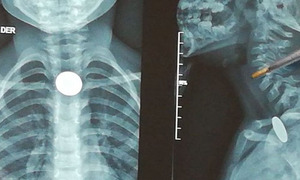

9 2 1

Ocho niños y un adulto fueron sometidos a cirugías ORL en una jornada especial del Hospital General de Coronel Oviedo. Cortesía El Hospital General de Coronel Oviedo llevó adelante una maratón de cirugías otorrinolaringológicas, en la que un total de ... [Leer más]